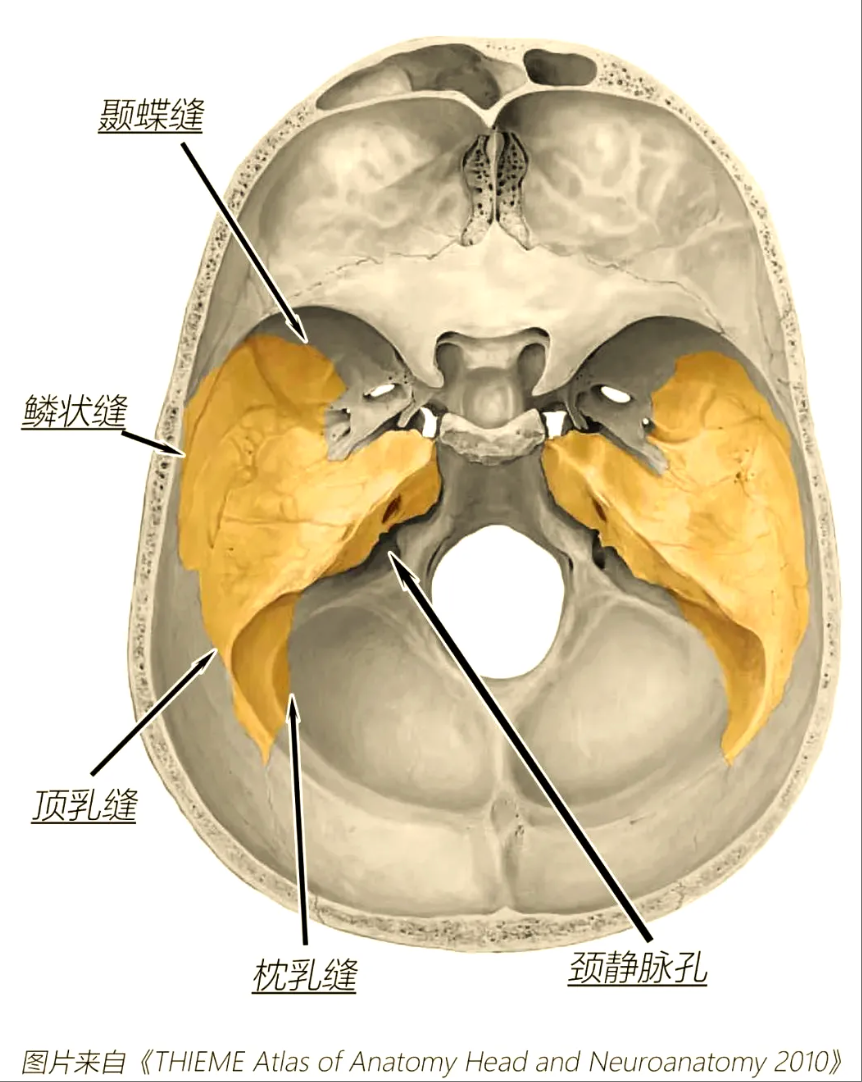

上海冬雷脑科医院脑血管专家盖延廷主任介绍:“颈静脉孔是颅底的一个骨性孔道,像一条至关重要的‘电缆管道’,里面有负责大脑血液回流的颈内静脉、负责大脑供血的颈内动脉等关键‘电缆’通过。

此例颈静脉孔巨大颅内外沟通肿瘤具有三重高危特性

一是贯穿颅内外,经颈静脉孔同时侵犯颅内和颈部,手术需要同时打开颅腔和颈部,解剖结构更复杂;

二是肿瘤血供异常丰富,10多根血管深入瘤体缠结,手术中将出血凶猛;

三是肿瘤区域与颈静脉孔中的‘电缆’、脑干紧密粘连,稍有不慎将导致神经受损,甚至呼吸心跳骤停。”